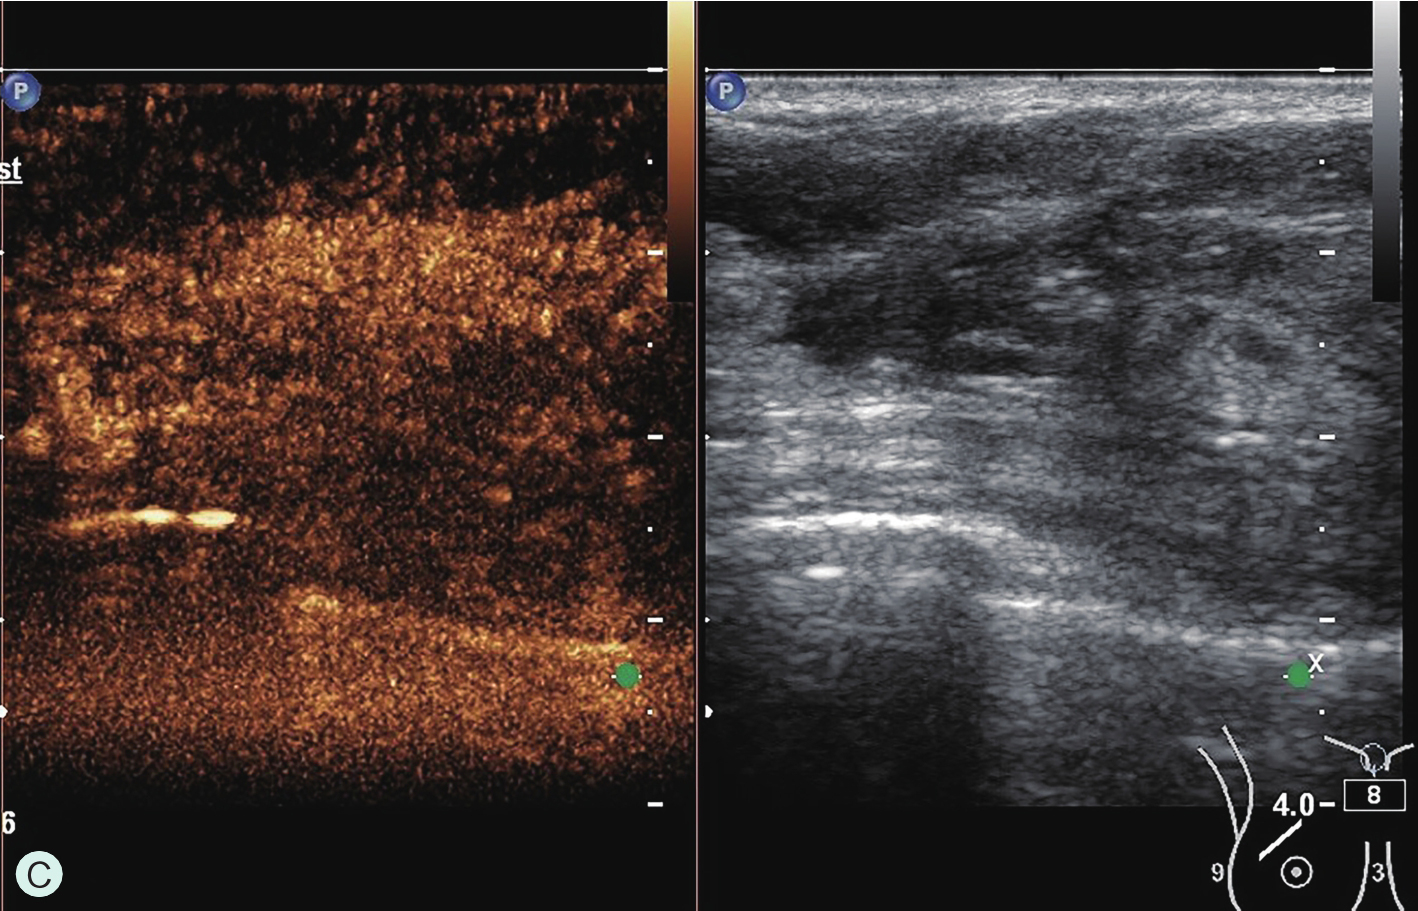

所有具有超声造影功能并支持浅表线阵探头造影的超声诊断仪器均可用于乳腺超声造影检查。由于乳腺超声造影对设备的造影效果、探头选择及参数调节要求很高,故在开展乳腺超声造影前,必须充分论证其造影效果,与设备应用专员共同调节造影参数至乳腺超声造影最佳模式。常规高频线阵探头不能用于乳腺超声造影,而必须选用低频线阵探头。下面将根据笔者所在单位临床工作实际,列举几种超声仪器的乳腺超声造影参数及所用探头供读者参考(图2-1-3~图2-1-7)。

图2-1-6 SAMSUNG RS80A乳腺超声造影参数及所用探头

A.SAMSUNG RS80A乳腺超声造影参数;B.SAMSUNG RS80A乳腺超声造影探头L3-12A